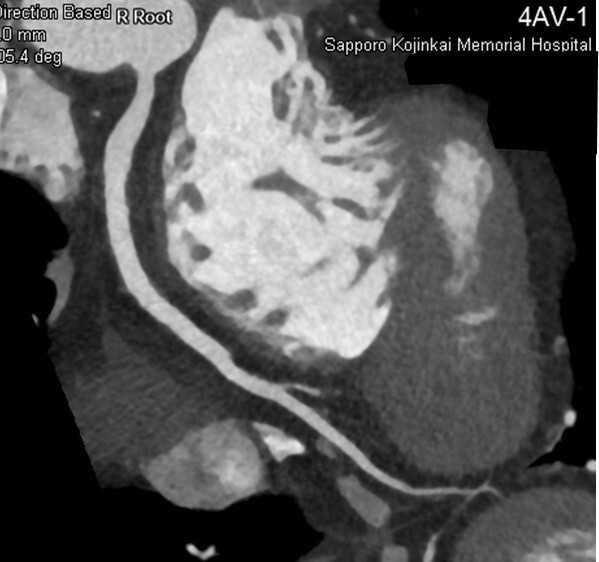

- コロナリーCT検査:外来で行うことができ、心臓を栄養している血管(冠動脈)の病変部位を検索する手段として最も簡便な方法です。造影剤を腕の血管から注入しながらCT検査を行います。

所要時間は10分程度です。(写真はコロナリーCT検査によって得られた画像)